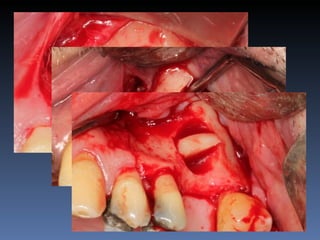

Maria Gomes Moraes

Idade – 53 anos

Sexo – Feminino

Raça – Caucasiana

ASA – II

Data- 23-04-2012

Diagnóstico: Atrofia severa

da pré-maxila.

Plano de tratamento: Aumento de volume horizontal

com blocos ósseos autógenos “onlay” provenientes do

Ramus da Mandíbula.

sutura nylon 4-0

Pós-operatório -5 dias